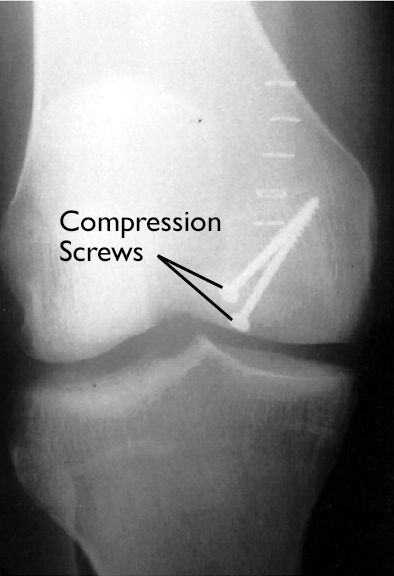

OCD lesion in knee fixed with screws

In this X-ray of the knee, an OCD lesion has been fixed in place with two screws.

Reproduced with permission from Crawford DC, Safran MR: Osteochondritis dissecans of the knee. J Am Acad Orthop Surg 2006; 14: 90-100.